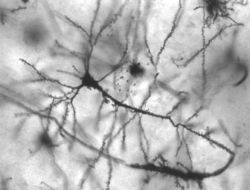

وتتصل بلايين العصبونات بعضها ببعض، بشبكات معقدة. ويعتمد أداء كل الوظائف العقلية والجسدية على ترسُّخ الشبكات العصبونية والحفاظ عليها. فعادات الشخص ومهاراته – مثل عض الأظافر أو العزف على آلة موسيقية- تكون مغروسة في الدماغ، داخل الشبكات العصبونية، المنشطة باستمرار. وعندما يقف الشخص عن أداء نشاط معين، تتوقف الشبكات العصبية الخاصة بذلك النشاط عن العمل، وقد تختفي في النهاية.

والعصبونات، مثل سائر الخلايا، محاطة بغشاء رقيق يكون الطبقة الخارجية، مع فارق أن غشاء العصبونات مُعَد بشكل خاص لنقل الدُفْعات العصبية. ويتكون العصبون من جسم خلوي وعدد من الألياف الأنبوبية الشكل. ويحمل أطول الألياف، الذي يسمى الجسم الخلوي، الدفعات العصبية من الجسم الخلوي إلى العَصْبُونات الأخرى. وتلتقط الألياف المتفرعة القصيرة، والتي تسمى التغصنات، الدُفْعات العصبية من محاوير العصبونات الأخرى إلى الجسم الخلوي. أما المشابك فهي المواضع التي تنتقل فيها الدُفعات العصبية بين الفروع العصبونية. وقد يكوِّن كل عصبون مشابك مع آلاف الخلايا العصبية الأخرى.

تغطي بعض المحاوير طبقة من مادة دهنية تسمى الميلين، وظيفتها عزل الألياف العصبية وتسريع انتقال الدُفْعات العصبية على سطحها. والميلين أبيض اللون، وتكوِّن المحاوير البيضاء المحزومة بإحكام داخل الميلين ما يعرف باسم المادة البيضاء. أما أجسام الخلايا العصبونية والمحاوير الخالية من الميلين، فهي تكوِّن المادة الرمادية للدماغ. وتتكون القشرة المخية من المادة الرمادية، بينما يتكون معظم الجزء الباقي من المخ من المادة البيضاء.

تحاط العصبونات بالخلايا الدبقية، وهي خلايا يعتقد أنها الإطار الداعم للعصبونات. وتؤدي الخلايا الدبقية أيضًا وظائف أخرى هامة. فبعضها، على سبيل المثال، يجعل الدماغ خاليًا من العصبونات المصابة أو المريضة؛ وذلك بابتلاعها وهضمها. وبعض الخلايا الدبقية تنتج أغطية الميلين التي تعزل بعض المحاوير. وتشير بعض الدراسات المعملية إلى أن الخلايا الدبقية، تنقل أيضًا، مثل العصبونات، بعض الدفعات العصبية.